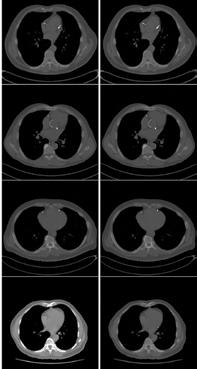

UCSF collaborated with 20 sites worldwide using federated learning to develop a model for predicting COVID-19 outcomes from chest X-rays, labs and vitals collected during an emergency room visit. Remarkably, the modeling was completed in 5 months and achieved an average area under the curve (AUC) >0.92 for predicting outcomes at 24 and 72 hours from time of presentation (Nature Medicine; 27, pages 1735–1743. 2021). The project demonstrated the power of AI methodologies combined with federated learning to collaboratively develop robust solutions to critical public health problems in a timely fashion. The work has since paved the way for a multi-center effort focused on predictive modeling in prostate cancer (PI: Peder Larson, PhD, UCSF/UCLA).